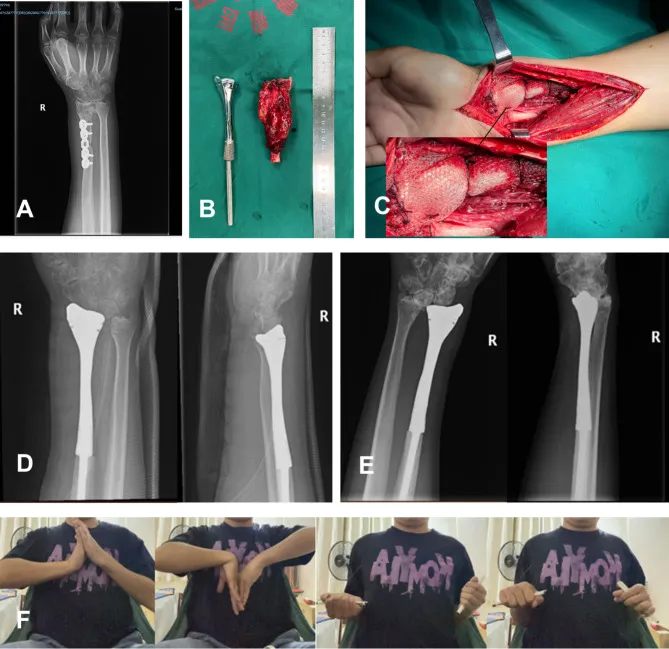

广西医科大学附属医院的研究人员在2018年1月至2021年1月期间,为五名桡骨远端骨巨细胞瘤患者实施了创新的手术治疗方案。

他们使用3D打印技术制造了带有网状补片的定制钛合金假体,以精确匹配每位患者的解剖结构。

在手术过程中,肿瘤被仔细切除,同时尽可能保留关节囊和周围韧带。

假体柄部分集成了纹理表面和凹槽以优化骨水泥固定,远端部分则忠实地复现了桡骨的自然形态,并预制了孔洞用于韧带的牢固附着。

经过平均40.8个月的随访,患者显示出有意义的功能恢复。

腕关节活动度平均为背伸20°,掌屈21.6°,旋前71.2°,旋后50°,握力达到健侧的64%。

未观察到感染或假体松动,但研究中也报告了并发症。

两名患者出现桡尺远侧关节脱位,一名患者因轻微的假体位置不佳而出现了尺骨撞击综合征。